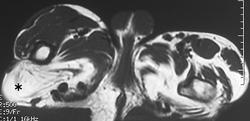

Клинические проявления заболевания характеризуются выраженным полиморфизмом. Наряду с типичной симптоматикой - парциальным гигантизмом рук и ног, гемигипертрофией, артериовенозными аномалиями, макроцефалией - наблюдаются разнообразные опухоли: бородавчатый эпидермальный невус, гемангиомы, лимфангиомы, липомы, гамартомы. Иногда отмечаются косоглазие, экзофтальм, миопия, прогения, варикозное расширение вен, разрастание кожи на подошвах. Примерно в 55% случаев выявляется умственная отсталость, в 13% - судорожный синдром. Наблюдались также больные с изолированной макродактилией, спленомегалией, избирательной патологией глаз и черепа в виде множественных менингиом, полимикрогирии, ретинальной пигментной дегенерации и атрофии зрительного нерва. Продолжительность жизни пробандов, как правило, невелика и колеблется от 3 до 40 лет. Смерть наступает чаще от злокачественных новообразований. Описаны такие опасные для жизни осложнения, как венозные тромбозы и эмболия легочной артерии. Так, A. Stavotinek и соавт. в 2000 г. сообщили о 3 больных, умерших в возрасте 12, 17 и 25 лет от эмболии легочной артерии [9].